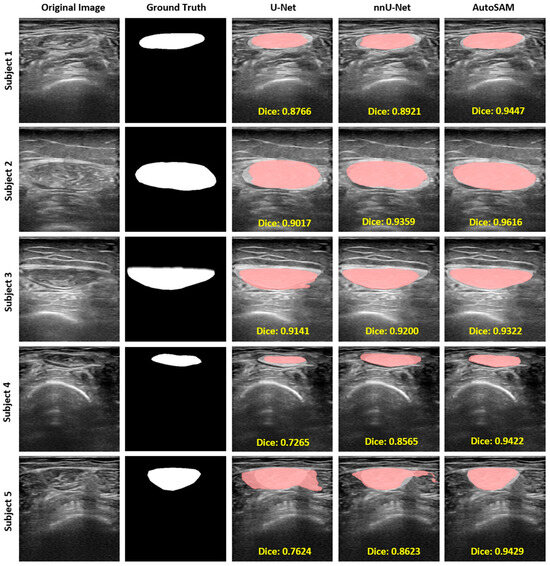

| Model | DICE | IoU | HD | Accuracy | Precision | Recall |

|---|---|---|---|---|---|---|

| U-Net | 0.8178 (SD = 0.1010) | 0.7035 (SD = 0.1371) | 4.2724 (SD = 2.6113) | 0.9637 (SD = 0.0175) | 0.9828 (SD = 0.0189)  | 0.9759 (SD = 0.0221)  |

| nnU-Net | 0.8910 (SD = 0.0610) | 0.8084 (SD = 0.0924) | 3.2074 (SD = 2.7506) | 0.9789 (SD = 0.0145) | 0.9881 (SD = 0.0143)  | 0.9884 (SD = 0.0142)  |

| Auto-SAM | 0.9205 (SD = 0.0449) | 0.8557 (SD = 0.0720) | 1.7213 (SD = 1.1670) | 0.9826 (SD = 0.0137) | 0.9897 (SD = 0.0109)  | 0.9911 (SD = 0.0141)  |